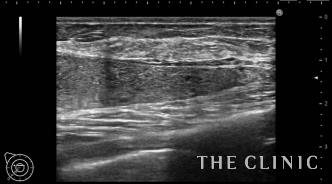

今回は、他院で非常に悲惨な治療をされた患者さんが来院したのでご紹介させていただきます。

この方は、ヒアルロン酸豊胸を受けた1か月後にコンデンスリッチ豊胸を受け、乳房の変形、しこりでお悩みになり、来院されました。

ご存じの通り、脂肪は血流がないと定着しません。大量のヒアルロン酸がある場合はそのまま脂肪を注入しても壊死してしまうので、ヒアルロン酸を溶解してから脂肪を注入します。

今回の症例はヒアルロン酸を溶解せず、脂肪を注入したためしこりになり、乳房が変形してしましました。

吸引後の画像です。ほとんどしこりはなくなりました。